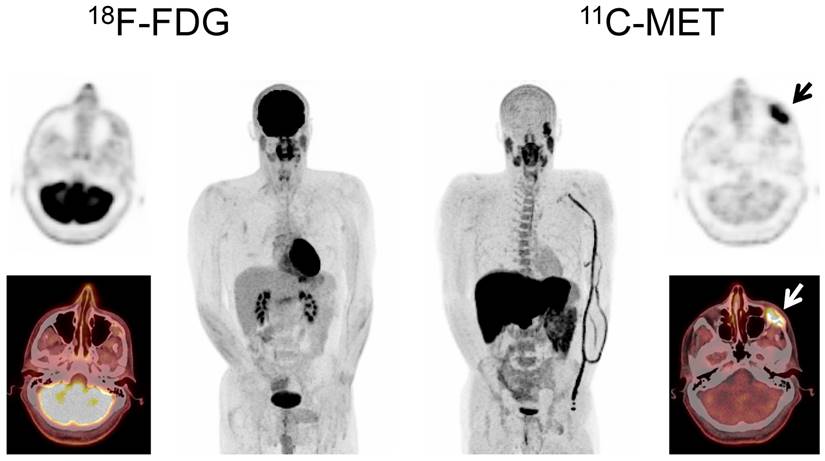

In PET/CT examinations with MET, MM lesions were detected in 59/78 patients (75.6%). In contrast, FDG did not identify any focal lesion in 31 patients (FDG-positive lesions in 47/78 patients, 60.3%; p<0.01). The 19 MET-negative patients corresponded to either cases in complete response (CR; n=13) or very good partial response (VGPR; n= 2) or cases with SMM (n=4). Of note, the remaining patient with SMM (patient #60) revealed increased MET uptake throughout the skeleton, whereas FDG-PET showed negative results (Figure 1).

Figure 1

Display of a patient (patient #8) with Ig G κ SMM. Imaging with both tracers was performed on the same day. Whereas PET/CT with FDG did not depict hypermetabolic foci suspicious for active MM, MET demonstrated increased tracer uptake throughout the skeleton. Bone marrow biopsy revealed 45% clonal plasma cells. Blood tests showed an IgG κ M-spike of 8.6 g/dl, free light chain (FLC) κ levels of 1.22 mg/dl, and FLC λ levels of 0.13 mg/dl (ratio κ/λ= 9.38). Bence-Jones proteinuria was 191 mg/24 h-collected urine. The patient was diagnosed of high-risk smoldering MM and started treatment in a Spanish myeloma group clinical trial. After induction and consolidation treatment, she is in stringent complete response with MRD negativity as assessed by flow cytometry.